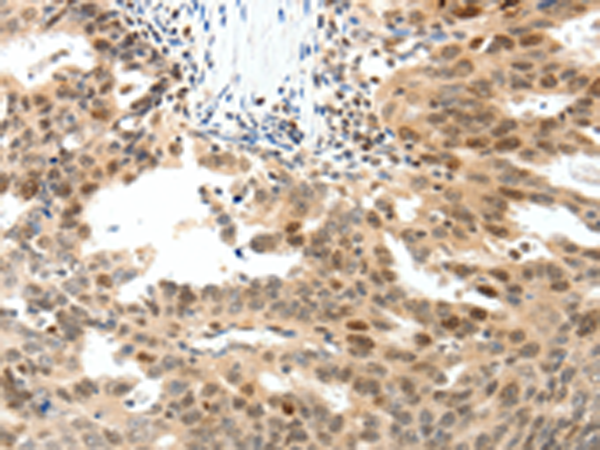

分类: 科研抗体货号: P04203别名: CRCS3; MADH7; MADH8应用: WB,IHC反应种属: Human, Mouse, Rat

分类: 科研抗体货号: P04238别名: NFAT3; NF-AT3; NF-ATC4应用: WB,IHC反应种属: Human, Mouse, Rat